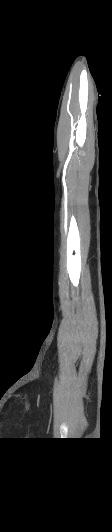

Мультиспиральная компьютерная томография является современным лучевым методом исследования, который позволяет с помощью рентгеновского излучения получить посрезовые снимки и после цифровой обработки создать объемные модели исследуемой области в мельчайших подробностях. Рентгеновские лучи в большей степени поглощаются плотными тканями организма, поэтому на снимках хорошо визуализируются кости скелета. Для оценки состояния мягкотканных структур в обязательном порядке проводится контрастное усиление.

Введение контраста требуется для лучшей визуализации мягких тканей конечностей, включая мышцы, связки, лимфатические узлы, нервные стволы и сосудистую систему и назначается для выявления воспалительных процессов, сосудистой патологии, при подозрении на опухолевые образования.

Йодсодержащий контрастный препарат вводится внутривенно, после чего он хорошо окрашивает кровеносные сосуды. Так как патологические очаги, и особенно опухолевые образования, имеют развитую сосудистую сеть, за счет этого они отчетливо контрастируют на фоне здоровых тканей. Методика контрастирования позволяет проводить точную и достоверную диагностику патологических процессов мягких тканей конечностей, включая опухоли на ранних стадиях развития, когда значительно выше шансы пациента получить эффективное лечение.

В наших медицинских центрах КТ верхней конечности с контрастом выполняется на современных мультиспиральных компьютерных томографах экспертного уровня TOSHIBA AQUILION. Аппараты послойно сканируют область исследования, одномоментно выполняя множество тончайших срезов. В результате получаются снимки высокого качества и трехмерные модели с изображением костного скелета и мягких тканей конечностей. При этом методика скоростного мультисрезового сканирования обеспечивает минимальную дозу рентгеновского облучения для пациента.